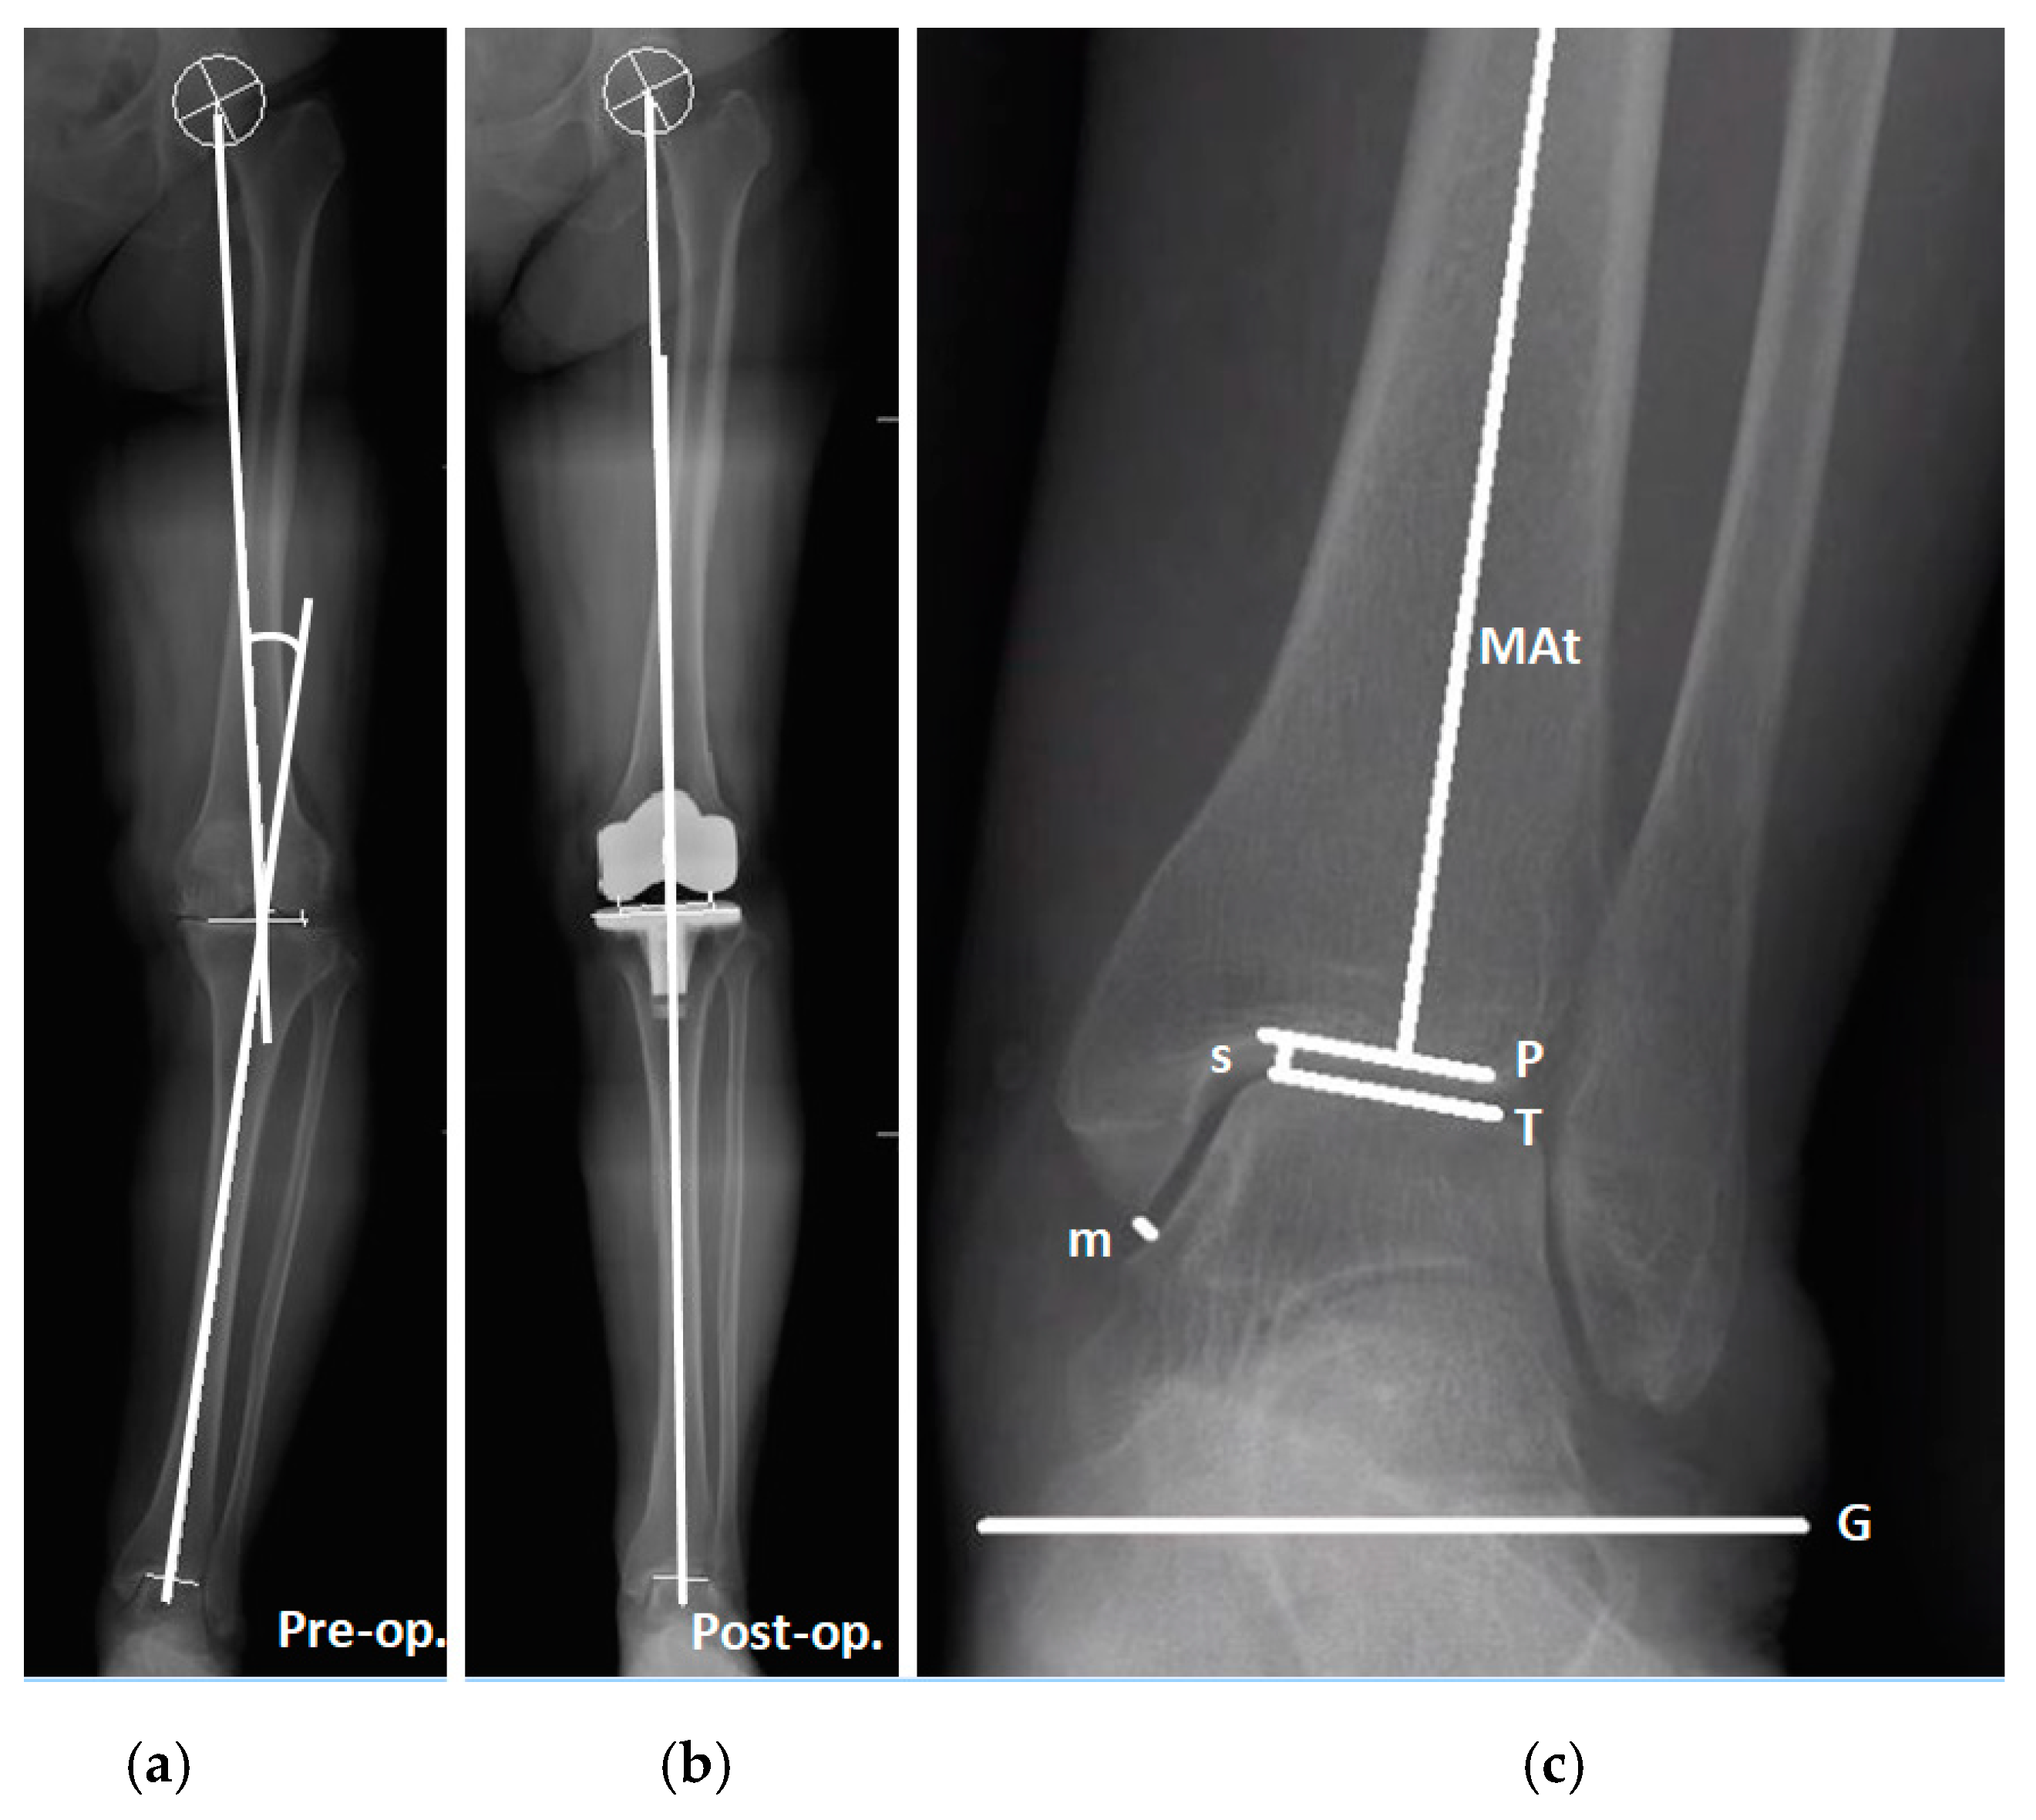

:1. Introduction

2. Materials and Methods

2.2. Study Grouping and Parameters of Knee and Ankle

2.3. Radiographic Measurements